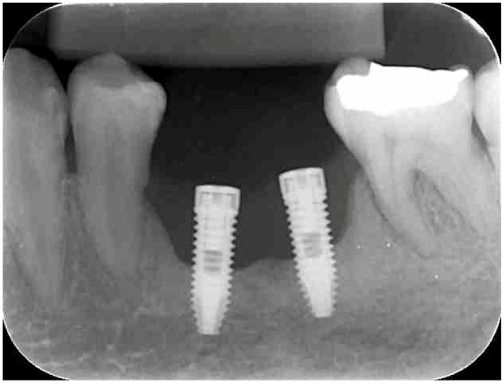

Figura 2: radiografia periapical seis meses após a colocação dos implantes, confirmando a perda óssea na altura do terço médio das fixações. Observar o provável nível gengival na altura da cabeça dos implantes, representado por uma área menos radiolúcida (quase um tom de cinza) na área onde houve a reabsorção.

Analisando as radiografias e confiando na avaliação clínica da colega, onde não há profundidade da sondagem, tão pouco sangramento, podemos suspeitar que houve uma reabsorção primária desse osso, devido a pouca espessura óssea e a formação de um tecido mole (possivelmente conjuntivo) que está aderido as roscas do implante. Vale lembrar que tudo isso são suposições baseadas apenas nas imagens radiográficas e nas informações passadas pela nossa colega dentista.